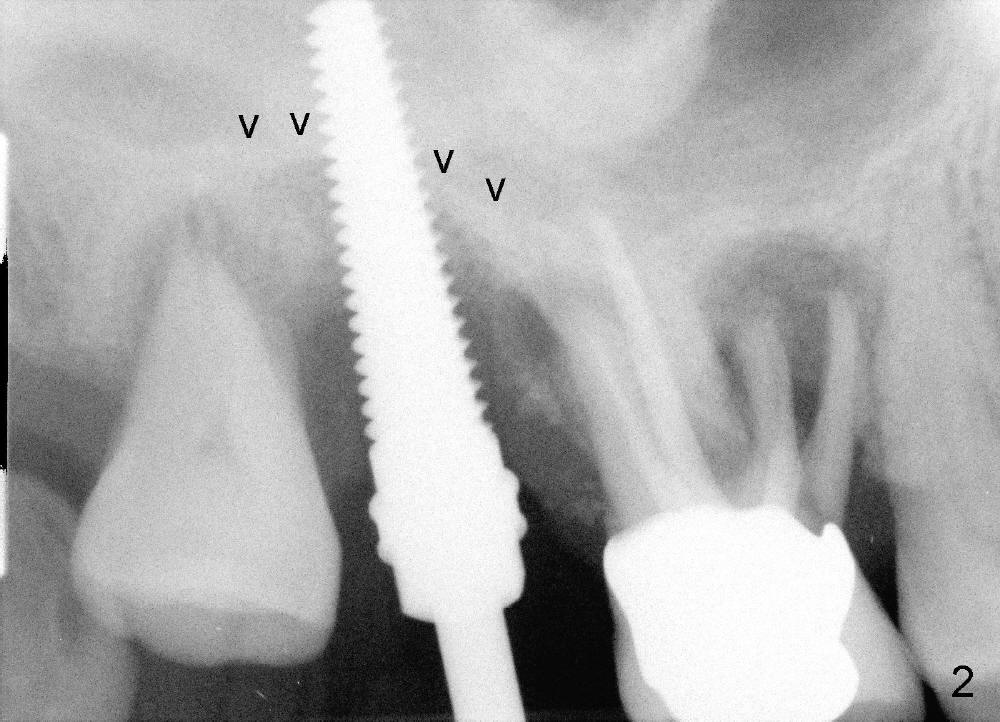

The upper right molars are deemed non-salvageable in a 60-year-old man (Fig.1). The tooth #2 is symptomatic. It is treated first. After extraction, osteotomes are used to create osteotomy (bone being solid) and sinus lift, followed by insertion of tap (Fig.2: 4.5x20mm). Arrowheads in Fig.2 indicate the upper border of the sinus floor. It appears that instrument is intruded too much into the sinus. Clinically the sinus membrane is perforated, as shown by nose blowing. The next bone manipulation instruments (taps 5-7 mm in diameter) should be shortened (17 mm). Fig3 shows a 7x17 mm tap in place with stability. Placement of 7x17 mm implant is associated with sinus lift (Fig.4 arrowheads).